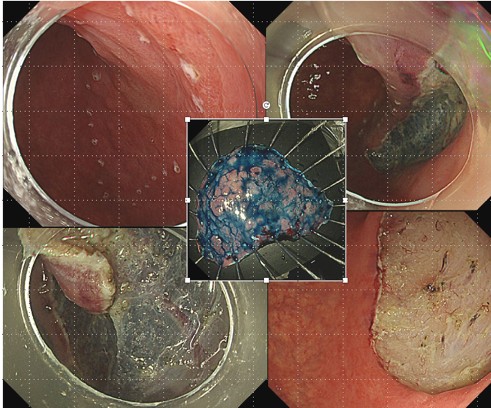

内視鏡センターとして、胃がん・大腸がん、食道がん・十二指腸がんの早期診断・治療に重点を置いています。早期がんに対しては、内視鏡治療(ESD:内視鏡的粘膜下層切開剥離術、EMR:内視鏡的粘膜切除術)を実施しています。これらの内視鏡治療は専門性が高く、外科手術に比べて負担が小さく入院期間も短期です.がん以外の疾患では、出血性胃潰瘍・十二指腸潰瘍、食道静脈瘤破裂、急性胆管炎、大腸・食道狭窄、嚥下障害に対して必要な内視鏡治療(止血術、胆管ドレナージ術、ステント挿入術、胃ろう造設術)を行っています。

消化管疾患の診断・治療に用います.特に早期がん,大腸ポリープの診断・治療には,通常光観察に加え,粘膜表層の毛細血管や粘膜微細模様を強調表示するの特殊光観察(NBI: narrow band imaging)機能を搭載した内視鏡システムが有用です。

写真:オリンパス社製電子内視鏡システム(EVIS X1) /上部:EZ1500・XZ1200・HQ290・H290T・1200N、下部:XZ1200I・H290ZI、側視鏡:Q290V

上部消化管内視鏡1375例

下部消化管内視鏡628例

内視鏡的消化管腫瘍切除術(ESD・EMR)120例